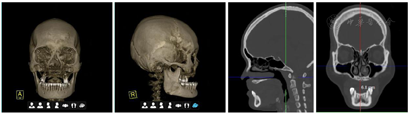

X线片和颌面CT检查发现双侧下颌角肥大、上颌骨重度骨缺损。

专科检查:双侧颧骨、下颌角过大,面中部凹陷。上唇唇正中可见术后瘢痕,红唇菲薄、唇珠消失(图1)。恒牙列,16-25缺失,17近中牙根外露,I°松动,26牙近中牙冠缺损。患者缺牙区牙槽突不平整,前庭沟变浅,水平向、垂直向咬合关系丧失(图2)。

全口曲面断层片示16-25牙缺失(图3)。标准头颅侧位X线片以及头影测量分析结果显示上颌牙槽骨水平向骨缺损伴骨性反颌(图4)。CT结果显示上颌缺牙区牙槽骨缺损,骨性反颌。上颌16牙位窦嵴距离约1 mm,上颌前牙区牙槽骨高度不足7 mm,双侧下颌角肥大,呈方脸形态(图5)。